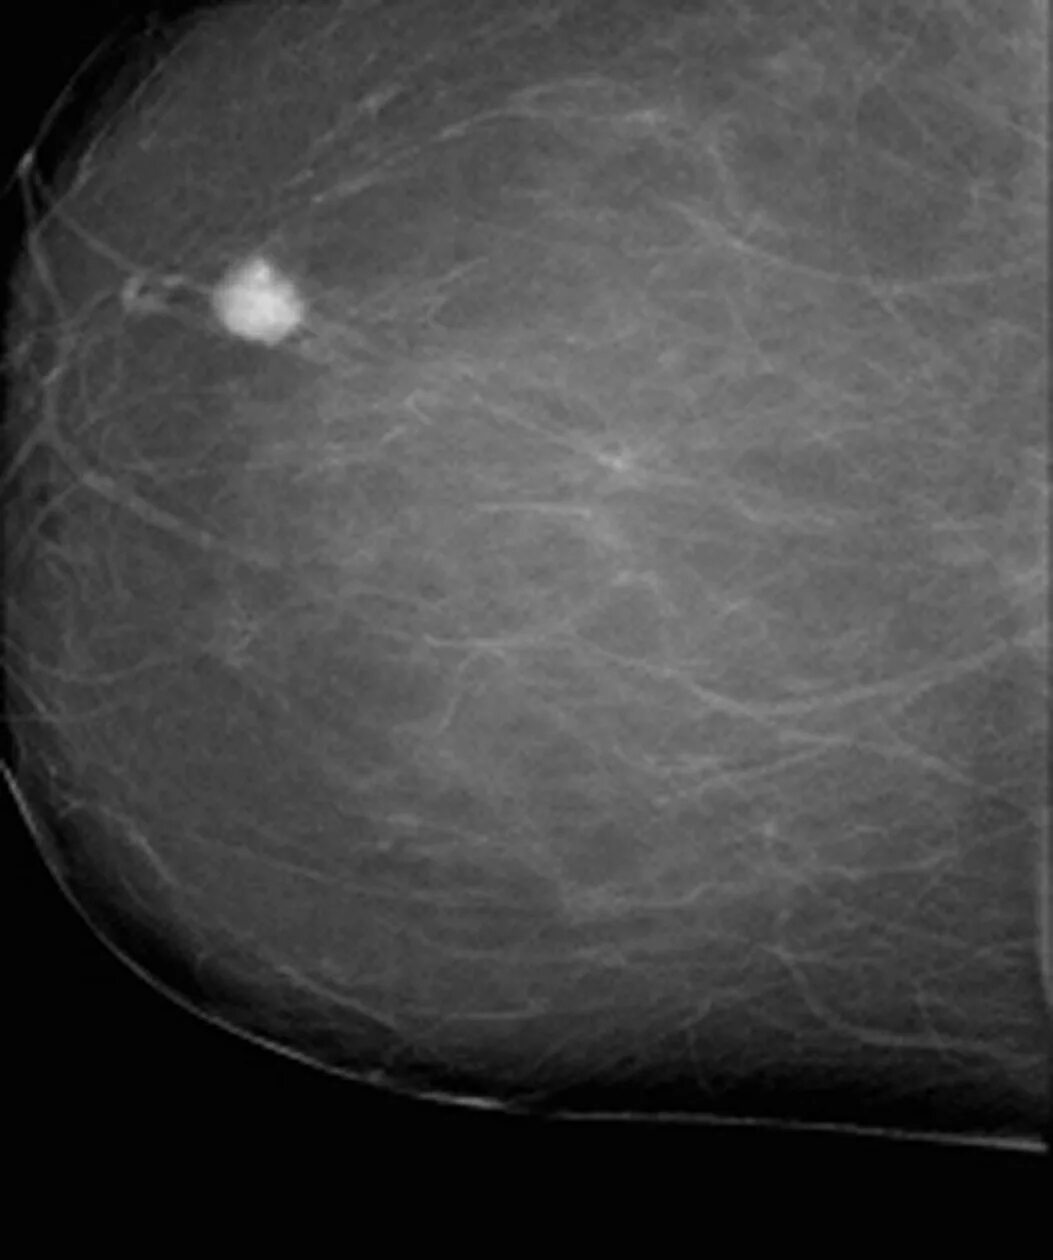

Как выглядит киста молочных желез